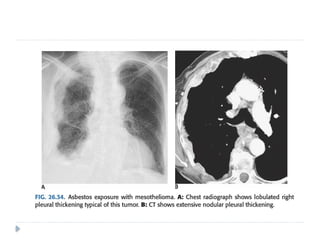

MALIGNANT MESOTHELIOMA

On imaging :

⚫ Diffuse nodular pleural thickening – pleura along the

intercostal spaces, costophrenic angles and lung apices

are involved.

⚫ Pleural plaques (latent period of formation is 20yrs; strong

indicator of asbestos exposure): usually seen adjacent to ribs.

Involving sixth to ninth rib. These themselves are not

premalignant

⚫ Pleural effusion

⚫ Calcifications may be seen along diaphragmatic pleura.